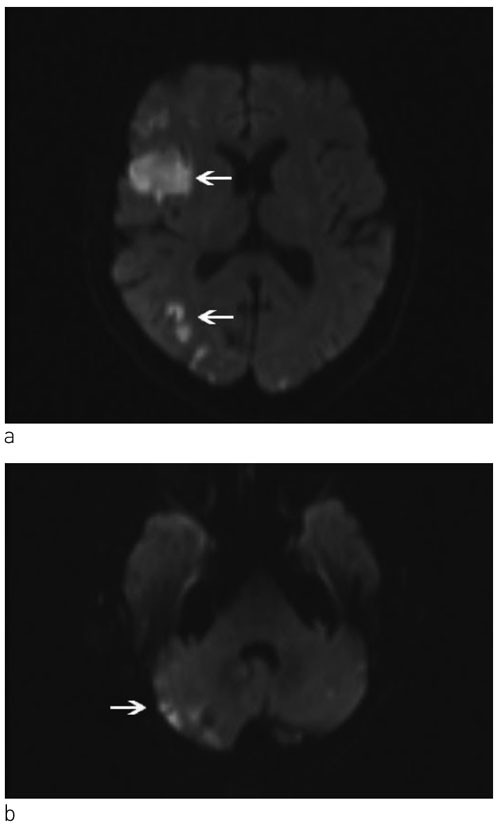

Tre uker etter sykdomsstart fikk pasienten igjen synstap og forverring av rom-retningsvansker. Dette førte til ny innleggelse i nevrologisk avdeling. Klinisk hadde hun høyre homonym hemianopsi, økt apati og apraksi. Hun trengte hjelp til å finne frem i avdelingen. MR av hjernen viste flere nytilkomne iskemiske lesjoner, D-dimer var > 20 mg/l (normalt 0,00 – 0,50) og troponin-T hadde økt til 0,27 µg/l (normalt < 0,03). CT av thorax, supplert med CT av abdomen, viste infarkter i nyre og milt, forstørrede binyrer og vekst av lymfeknutene i mediastinum. INR ved innleggelse var 1,6.

Operativ behandling av primærtumor i lungen ble vurdert, men til tross for kombinasjonsbehandling med dalteparin og acetylsalisylsyre fikk pasienten i påvente av operasjon akutt venstre hemiparalyse, forverring av kognitiv svikt og ble helt pleietrengende. Hun hadde D-dimer > 20 mg/l (normalt 0,00 – 0,50) og troponin-T 3722 ng/l (normalt < 15). MR av hjernen viste et stort infarkt i høyre a. cerebri medias forsyningsområde (fig 2). Pasienten ble tverrfaglig vurdert som inoperabel på grunn av et aggressivt forløp med raskt tilbakevendende og multiple organtromboser. Risikoen for nye tromboemboliske hendelser som følge av perioperativ seponering av antikoagulasjonsbehandling ble vurdert som høyere enn den mulige operative nytten. Hun ble utskrevet til sykehjem og fikk palliativ strålebehandling mot mediastinum og høyre fossa supraclavicularis på grunn av infiltrative lymfeknuter subcarinalt, pretrakealt og i øvre høyre mediastinum. Som komplikasjon til hjerneinfarktene utviklet hun epilepsi. Klopidogrel ble kombinert med dalteparin og acetylsalisylsyre på grunn av akutt hjerteinfarkt med ST-segmentelevasjon under denne innleggelsen. Til tross for aggressiv antikoagulasjonsbehandling rapporterte datteren senere om en forbigående episode hvor det paretiske venstre beinet ble smertefullt, hvitt og kaldt, suspekt på perifer arteriell emboli. Ett år etter sykdomsdebut døde pasienten av hjerte- og lungesvikt betinget av betydelig tumorvekst. Autopsi ble ikke utført.